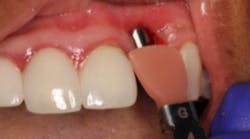

Case No. 1

This patient presented with an unrestorable tooth No. 10 due to severe caries (figure 1). Prior to tooth extraction, the patient was informed that in order to avoid having a large defect, additional bone and soft-tissue grafting would be necessary. This type of augmentation would require additional time and finances, as well as increased surgical visits and appointments. The patient was informed that failure to undergo these procedures might result in (1) longer restorations, (2) the need for gingival ceramics, (3) inability to clean the prosthesis, and (4) increased forces on the implant because of the increased crown-to-implant ratio.

After considering her options, the patient chose not to have additional grafting. The reasons for her decision were her low smile line, a desire to keep case cost and time to a minimum, and her interest in function over esthetics.